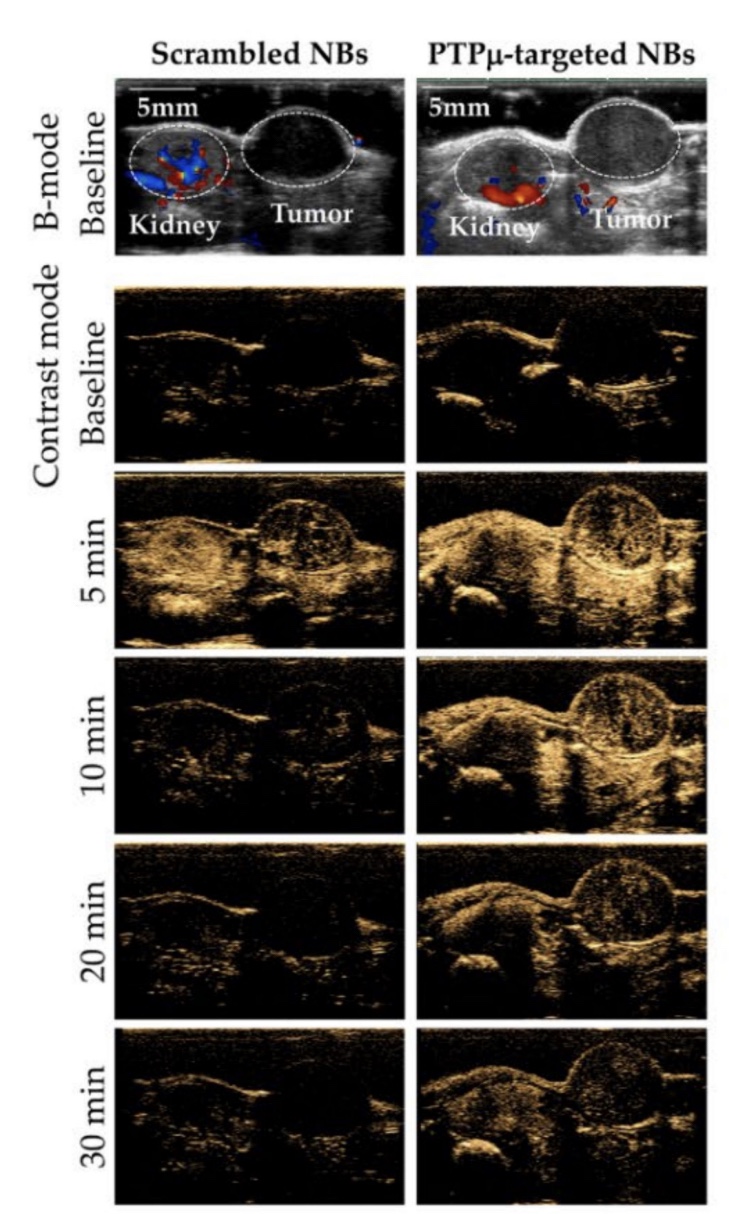

2️⃣ 이번에는 종양을 가지는 마우스를 대상으로 1에서와 동일한 방식으로  "무작위 NB 와 PTPmu 를 표적하는 NB 의 초음파 영상에서 나타나는 차이점" 을 알아봤어요.

첨부 이미지

✔️신장과 종양의 초음파 영상을 획득하여 관찰해 본 결과,

• 서로 다른 장기에 따른 초음파 영상에서의 유의미한 신호 강도의 차이는 발생하지 않았지만,

• 대조군과 실험군 간의 초음파 영상 신호 강도의 차이가 분명하게 보여요!  (CEUS: contrast-enhanced ultrasound)

무작위 NB 에 비해 PTPmu 표적 NB 는 시간이 지남에 따라 신호 세기가 더 천천히 줄어드는 양상을 보이고 있어요.

따라서, 종양을 가진 마우스에서는 무작위 NB 에 비해 PTPmu 를 표적하는 NB 를 활용하면 초음파 영상에서 더 긴 시간 증가된 세기의 신호를 관찰 할 수 있어 검사하기 편리하다고 할 수 있습니다.